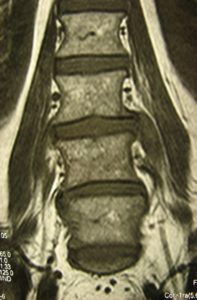

Μαγνητική Τομογραφία της Ο.Μ.Σ.Σ. (13/06/2007) Ακολουθία Τ1 και Τ2

Οβελιαία τομή (α,β) Παρατηρείται η ύπαρξη Επισκληριδίου Αποστήματος στο επίπεδο Ο3-Ο4 που προκαλεί μεγάλη στένωση του σπονδυλικού σωλήνα, με απώθηση του νωτιαίου σάκου. Διαπιστώνεται επίσης η ύπαρξη παρα-σπονδυλικού αποστήματος

Εγκαρσία τομή (γ,δ) Παρατηρείται η ύπαρξη Επισκληριδίου όπως επίσης και προ-παρασπονδυλικού αποστήματος.